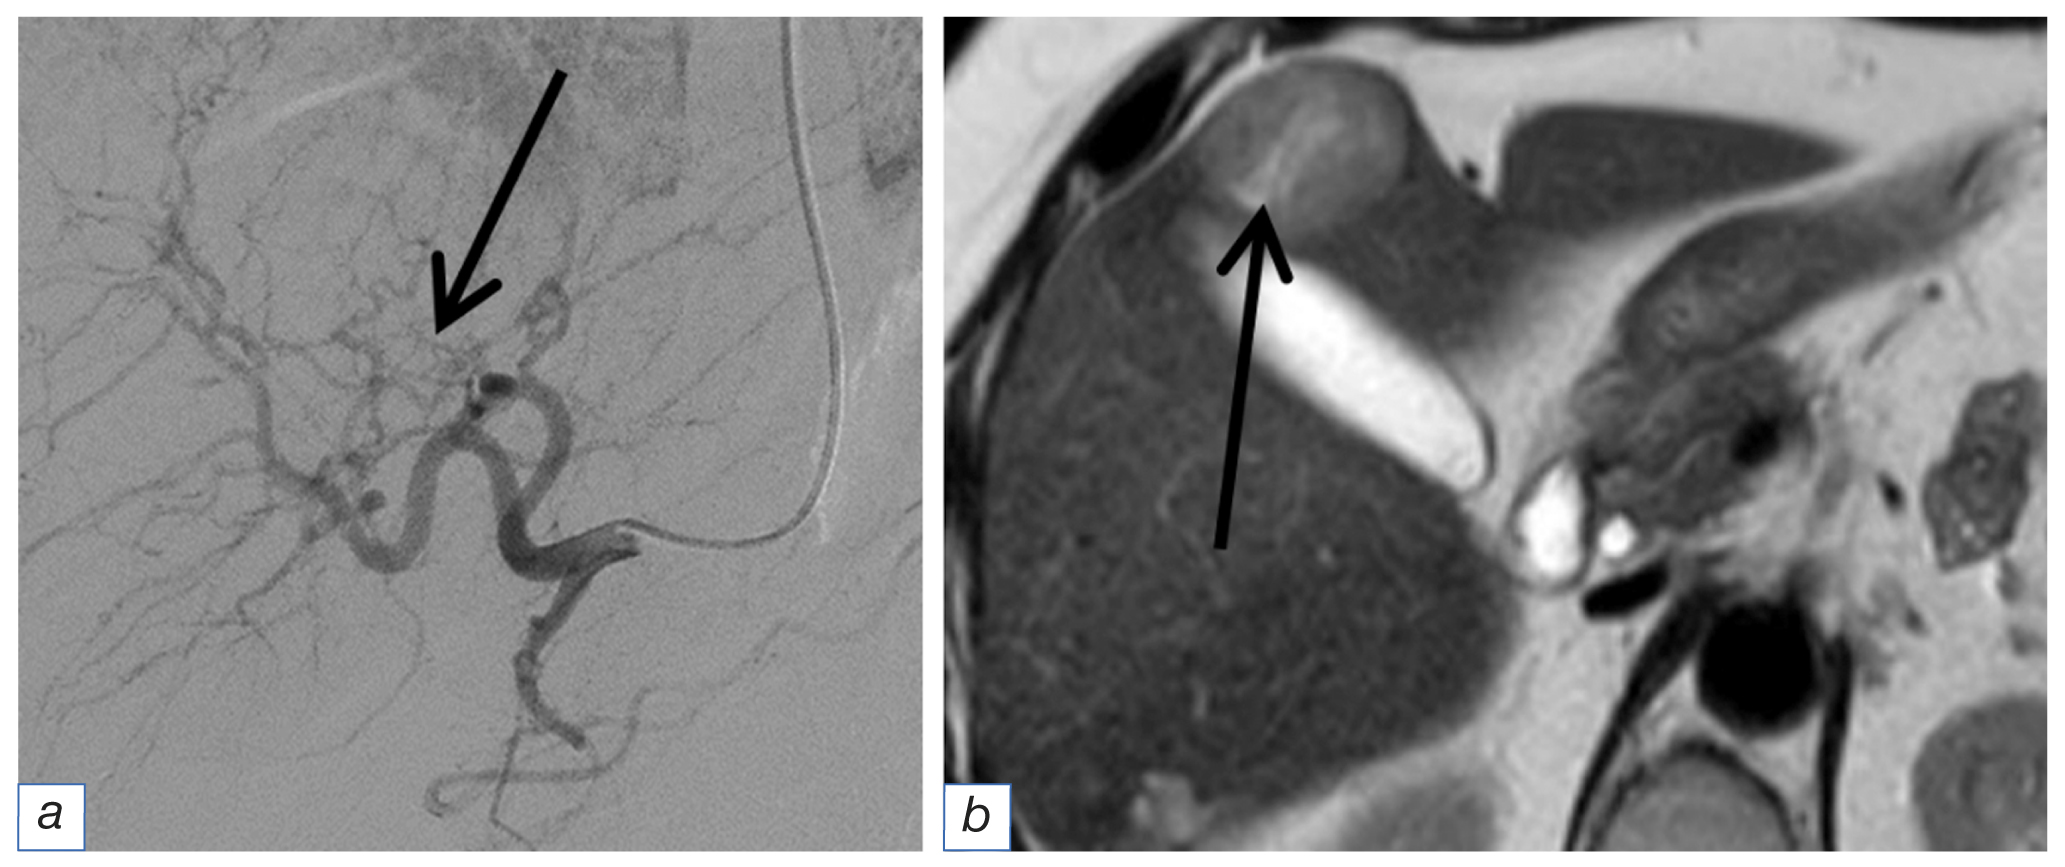

The angiographic image obtained during surgery was diverse. In some cases, we observed intense contrast of the metastasis parenchyma with a branched network of afferents (Fig. 2), whereas adjacent foci were only detected by recalibrated vessels originating in an atypical location (Fig. 3). In several observations, no angiographic signs of the tumor were observed. In such cases, the radiologist could only rely on the data from the diagnostic methods. The angioarchitectonics of the main tumor did not match the angiographic picture of liver metastases.

Fig. 3. The same patient. Angiographic picture of another metastasis with a diameter of 3 cm (а): several thin recalibrated vessels (arrow) exiting in an atypical place; magnetic resonance imaging of the same metastasis (b): slit necrosis in the structure (arrow).